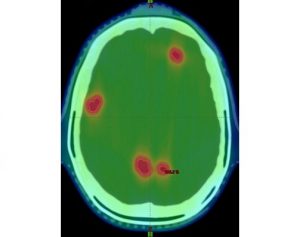

Mehr erfahren zu: "Stereotaktische Radiochirurgie bei Hirnmetastasen: Vorteile im Vergleich zur Ganzhirnbestrahlung" Stereotaktische Radiochirurgie bei Hirnmetastasen: Vorteile im Vergleich zur Ganzhirnbestrahlung Hochdosiertes, zielgerichtetes Bestrahlen von Hirnmetastasen beeinträchtigt das Gedächtnis weniger als eine aufwendigere Ganzhirnbestrahlung und kann zudem bei Bedarf später erneut eingesetzt werden. Das zeigt eine Nutzenbewertung durch das Institut für […]